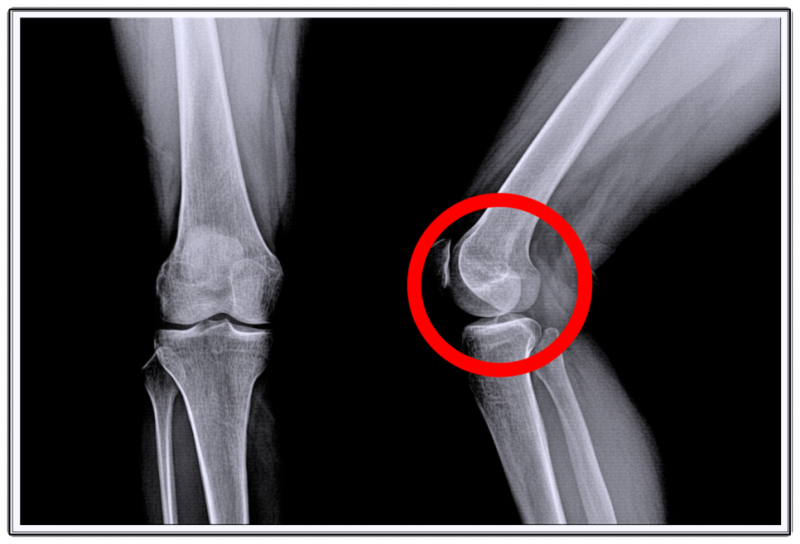

연골은 왜 자연 회복이 어려울까?

연골은 혈관이 거의 없는 조직입니다.

피부나 근육처럼 혈류를 통해 영양 공급을 받지 못하기 때문에

한 번 손상되면 재생이 어렵습니다.

특히 체중이 실리는 부위는 하중이 집중되면서 미세 손상이 반복되죠.

처음에는 가벼운 통증에 불과하지만, 점점 뻣뻣함과 걸림 느낌으로 이어질 수 있습니다.

방치하면 무릎 전체 균형이 무너지고,

연골 손상 상태가 점점 심해집니다.